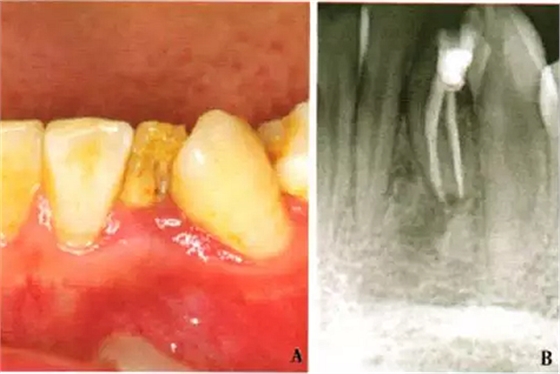

1周后,患者述疼痛消失。復(fù)診采用冷測壓方法根管充填(圖2),牙冠開髓孔處應(yīng)用Chem—flex(DentsplyDeTreyGmbH,Konstanz,Germany)充填。由于患牙牙冠形態(tài)異常,且唇側(cè)形態(tài)尚未恢復(fù);患牙周圍有牙石、軟垢,建議患者行牙周及修復(fù)治療以維持長期療效,被患者拒絕。9個(gè)月后隨訪,患者自述患牙經(jīng)治療后無癥狀,臨床檢查見32叩診正常,無松動;影像學(xué)檢查見32根尖周圍透射區(qū)域明顯減?。▓D3)。

A:32口內(nèi)像;B:X線片示32根尖周炎癥明顯減輕

圖3 左下側(cè)切牙9個(gè)月隨訪檢查